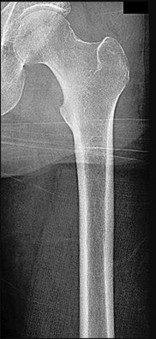

A 72-year-old female on prolonged bisphosphonate therapy presents with thigh pain.

Radiographs show a fracture of the femoral shaft. Which of the following radiographic features is most characteristic of an atypical femur fracture associated with bisphosphonate use?

Explanation

Atypical femur fractures (AFFs) associated with prolonged bisphosphonate therapy have specific major criteria defined by the ASBMR. These include a location anywhere from just distal to the lesser trochanter to just proximal to the supracondylar flare, transverse or short oblique orientation, non-comminuted (or minimally comminuted), and originating at the lateral cortex with localized periosteal or endosteal thickening ('beaking').